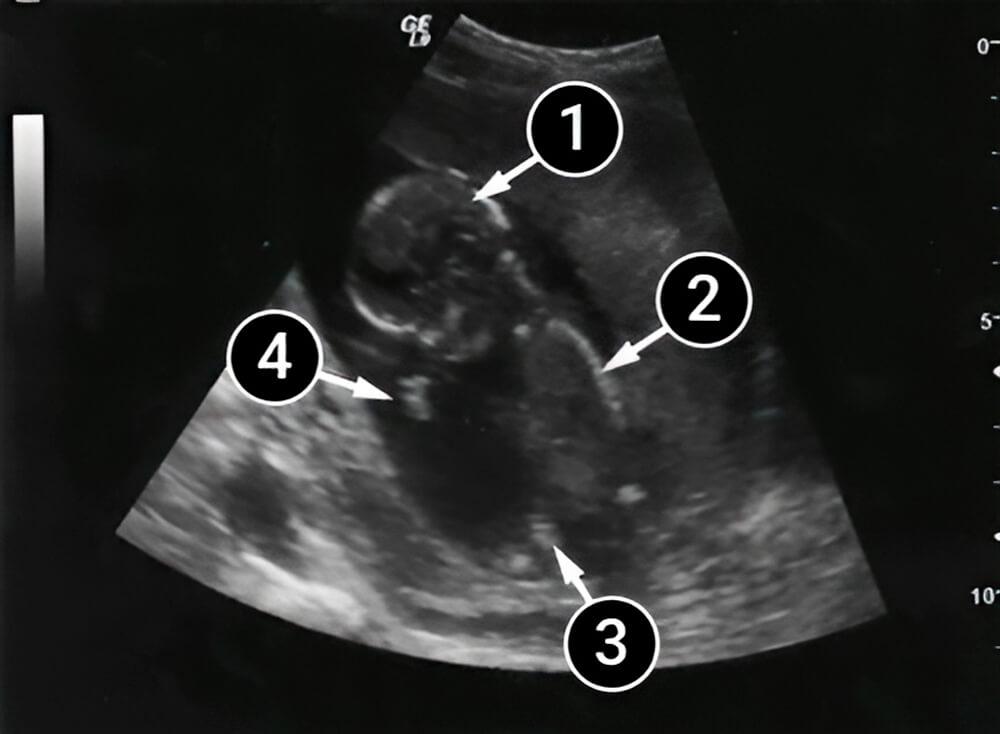

Las piernas del bebé están dobladas debido a la rápida formación de sus sistemas esquelético y muscular. ¡Ahora quiere moverse y ya puede tocar y rozar su propio cuerpo!

Los dedos de los pies, los talones y la columna son visibles en el ultrasonido. Los brazos del bebé están doblados y podemos ver tanto el codo como la mano izquierda, incluida la palma. También podemos ver los huesos del cráneo, el cuello y los hombros.